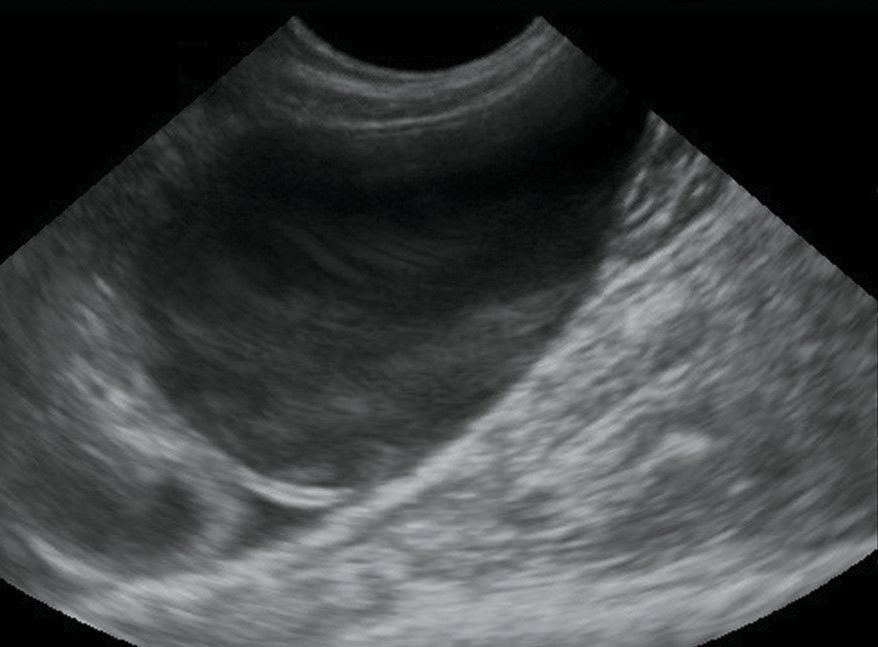

Epanchement abdominal important chez un chat atteint de PIF Symptômes de la PIF sèche L'évolution est plus lente et s'étend sur quelques moisDans la PIF sèche apparaissent des lésions inflammatoires appelées « granulomes » Leur répartition aléatoire dans les organes détermine une multitude de manifestations différentes Un épanchement pleural est une accumulation de liquide dans l'espace pleural Ce dernier est un espace situé entre les deux feuillets constituant la plèvre (double feuillet qui entoure et protège les poumons durant les mouvements respiratoires) L'épanchement pleural reconnaît de nombreuses causes chez le chat

épanchement abdominal chat-L'ascite est une accumulation anormale de liquide dans l'abdomen Cet épanchement liquidien est due à une maladie du foie, la cirrhose dans près de 80% des cas Pour mettre toutes les chances de votre côté face à la maladie, l'équipe médicale de Concilio vous accompagne personnellement dans toutes vos problématiques de gastro En plus, par perfusion, il sera au moins hydraté L'épanchement étouffe car il empêche les poumons de se remplir complètement et si ton chat ne bouge guère, c'est pour essayer de trouver un minimum d'air Il est important de déterminer l'étendue de l'épanchement et de voir s'il progresse ou par chance, régresse

L'ascite, également connue sous le nom d'épanchement abdominal, est le terme médical désignant l'accumulation de liquide dans l'abdomen du chien Cette condition peut provoquer des symptômes tels que des vomissements, une gêne abdominale et une perte d'appétit Un large éventail de causes peut provoquer une ascite, les traitements L' ascite est une accumulation anormale de liquide dans l'abdomen " On distingue 2 grandes causes, celles qui n'affectent pas directement le péritoine et celles qui sont la conséquence d'une atteinte du péritoine en luimême, complète le Professeur Silvain Dans le premier groupe, on trouve les maladies responsables d'une hypertensionBoutique L'ouvrage ECG du chien et du chat Diagnostic des arythmies s'engage à fournir à l'étudiant débutant ou au spécialiste en cardiologie une approche pratique du diagnostic électrocardiographique, ainsi que des connaissances approfondies, afin de leur permettre un réel apprentissage dans ce domaine qui a intrigué les

Request PDF Conduite à tenir devant un épanchement abdominal La cavité péritonéale est une cavité virtuelle baignée par une quantité L' épanchement péricardique est une accumulation anormale de liquide dans le sac péricardique, atteignant préférentiellement le chien plus que le chat On peut identifier 4 types de liquide un liquide hémorragique (dans la plupart des patients canins), un transsudat, un exsudat voire, dans de rare cas, un liquide chyleux